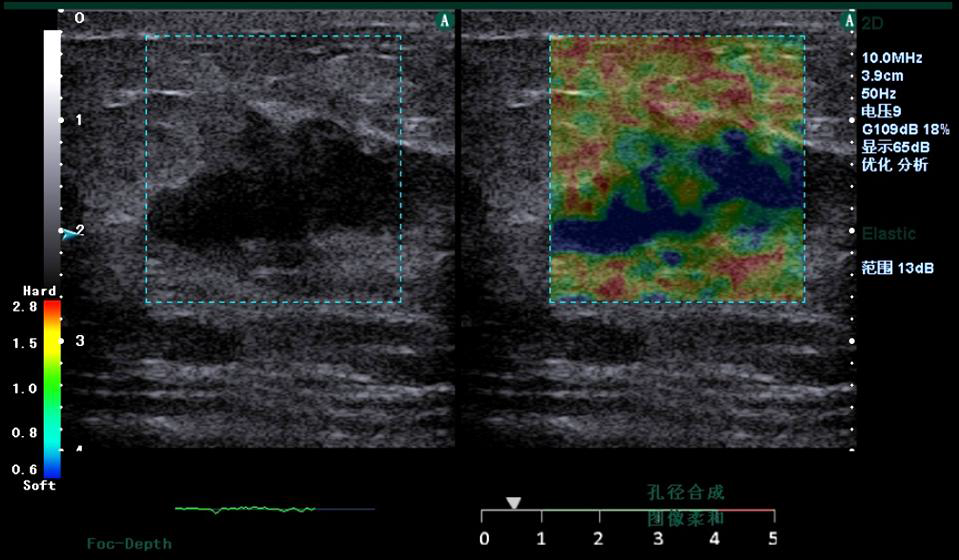

Figure 3. Clinical strain images of confirmed (a) inflammation lesion; (b) benign and (c) malignant breast tumor

2. Freehand elastography

Motion tracking of manual compression or breathing

induced movement generates a strain image

representing the elasticity of the underlying tissue. Statemed